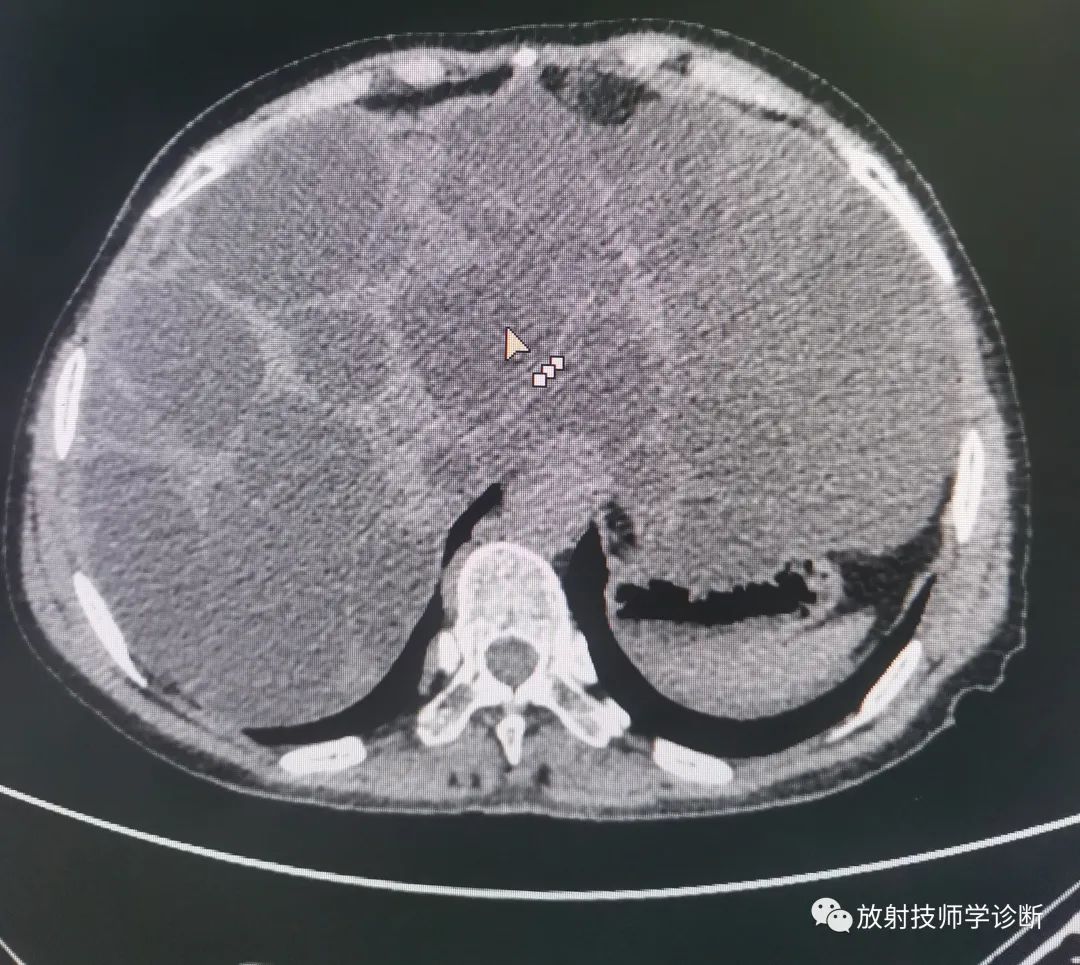

典型多囊肝

多囊肝,是一种常染色体显性遗传病,表现为肝脏的多发性弥漫损害,囊肿间的肝细胞正常,多合并多囊肾,同时在胰腺、脾脏、双肺及女性卵巢可发现囊性病变。多囊肝合并多囊肾致病基因位于人第16对常染色体上,DNA分析可作为疾病无症状时和产前的早期诊断。

(2)CT检查:可明确囊肿的大小、数目、解剖位置,并可发现1~2cm肝囊肿。CT平扫表现为肝内弥漫大小不一的水样低密度影,边缘光滑清楚,CT增强后无强化。

图片